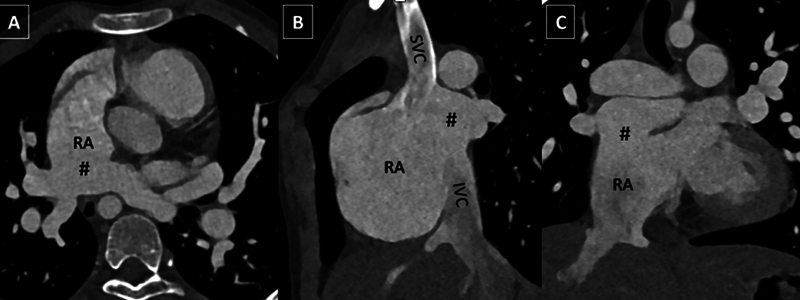

全肺静脉连接异常(TAPVC)是指所有肺静脉均异常排入体循环。心内型通常是所有肺静脉经冠状窦排入右心房。肺静脉直接与右心房相连的情况非常罕见,主要与右心房异位症有关。在此,我们介绍了一例罕见的 10 岁男童 TAPVC 病例,其特点是所有肺静脉均以非常规方式直接排入右心房,冠状动脉窦正常,无右心房异位。耐人寻味的是,计算机断层扫描成像显示出令人难以置信的罕见的肺部、血管和骨骼并存异常。这些畸形包括右肺无肺裂、左侧环状主动脉弓存在牛状分支模式、双侧颈肋骨和 C7 椎体融合异常。据我们所知,在 TAPVC 罕见引流模式的背景下,这种独特的并存异常组合以前从未在科学文献中报道过。

Total anomalous pulmonary venous connection (TAPVC) is anomalous drainage of all pulmonary veins into systemic circulation. The intracardiac type typically entails the drainage of all the pulmonary veins into the right atrium, via the coronary sinus. The connection of the pulmonary veins directly into the right atrium is exceptionally rare and has been primarily reported with right atrial isomerism. Herein, we presented a remarkable case of TAPVC in a 10-year-old male child, distinguished by an unconventional drainage of all the pulmonary veins directly into the right atrium, with normal coronary sinus and absent right atrial isomerism. Intriguingly, computed tomography imaging revealed a combination of incredibly rare coexistent pulmonary, vascular, and skeletal anomalies. These anomalies included absence of pulmonary fissures in the right lung, presence of left circumflex aortic arch with bovine branching pattern, bilateral cervical ribs, and C7 vertebral fusion anomalies. To our knowledge, this unique combination of coexistent anomalies has not been previously reported in scientific literature in the background of rare drainage pattern of TAPVC.